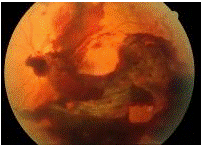

Một số bệnh nhân có thể có cảm giác có chớp sáng trước mắt, thường gặp trong trường hợp xuất huyết dịch kính có kèm theo các rách của võng mạc.Thăm khám lâm sàng cho thấy, bên cạnh các triệu chứng của chấn thương xuyên và chấn thương đụng dập nói chung (sẹo giác mạc, sẹo củng mạc, đục vỡ thuỷ tinh thể, lệch thuỷ tinh thể, máu tiền phòng…), có thể thấy sự xuất hiện của máu trong buồng dịch kính. Tuỳ theo mức độ máu trong buồng dịch kính, chúng ta có thể thấy máu trong buồng dịch kính có thể chỉ là một dải hoặc từng đám trôi nổi trong buồng dịch kính hay toàn bộ buồng dịch kính là máu. Trong trường hợp còn có thể quan sát được đáy mắt, có thể thấy một số tổn thương phối hợp của hắc võng mạc như xuất huyết hắc-võng mạc, rạn màng Bruch, rách võng mạc…